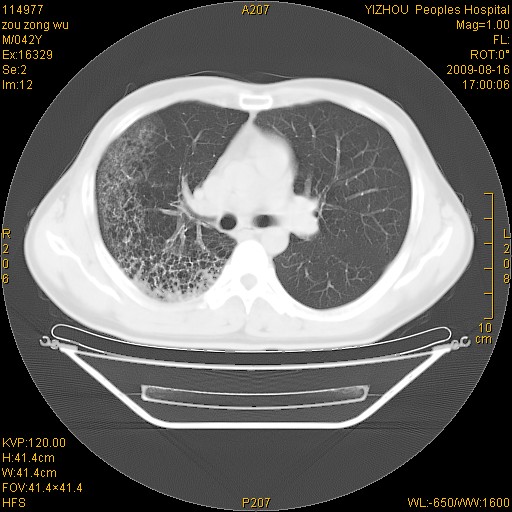

以下是引用zjzjr在2009-8-17 10:42:00的发言:[br]右侧间质性肺炎伴纤维化,右肺下叶肺囊肿伴感染(不除外外伤后引起),右肺野及胸壁软组织\\肝内见多发斑点状,中枪了吧.右侧胸膜肥厚\\粘连.